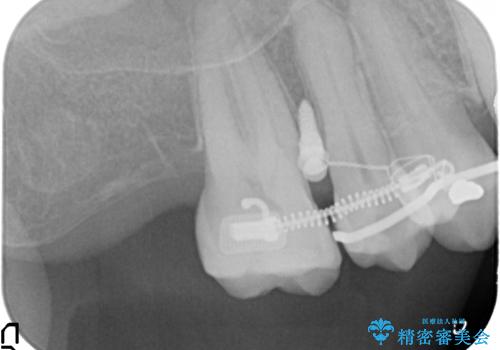

部分矯正を含む 歯周病治療 (再生治療・歯周ポケット除去・MTM・連結補綴)

検査の結果、強い歯ぎしりによる歯の周囲の骨の吸収が認められたため歯槽骨の再生・歯周ポケットの除去・力に対抗する連結補綴・補綴前処置としての小矯正を計画します。

特定の歯に強く力がかかりまた歯周病により臨床歯根が短くなっているような場合、歯の動揺を抑えるため連結補綴が検討されます。

歯の動揺が続くとより周囲の骨を失い最終的には歯を喪失してしまう可能性が高くなってしまうためです。

今回連結補綴を行うにあたり、歯周病の問題を解決するために再生療法・歯周ポケット除去手術を、またより歯の神経を保存し力に対抗できる環境を整えるために小矯正を行い精度の高いメタルボンドクラウンを製作することができました。